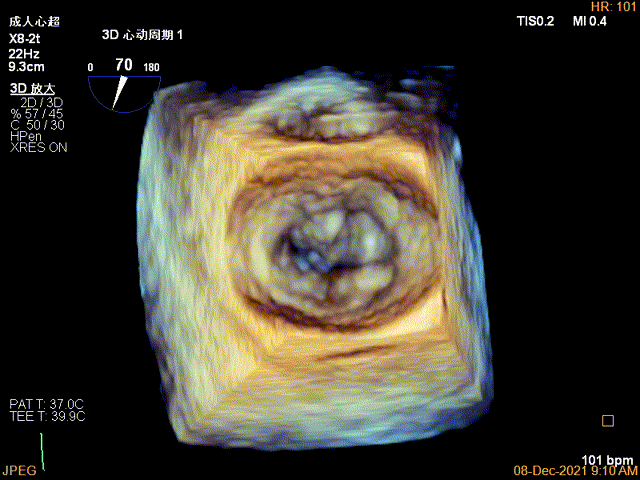

3D视图菲薄的卵圆窝,穿刺点位近似于3点位

3D视图下调整夹子位置及Rotate

3D-VIEW验证结果

1、此患者打破了风湿性心脏瓣膜患者不能做TEER治疗的传统观念,在经胸超声心动图的报告上风湿性心脏瓣膜病,二尖瓣瓣叶增厚,瓣口狭窄的初步印象让这个虚弱的患者险些错失了经导管介入治疗的机会。因此,对于每一个二尖瓣反流的患者,对其发病机制和解剖结构都需要全面细致的评估,即使是风湿性心脏瓣膜病变,也并非TEER治疗的绝对禁忌,利用经食道超声心动图的最新优势,结合2D、3D、 multivue、血流多普勒参数等多个维度去精准评估患者的解剖特征和血流动力学状态,为TEER治疗的可行性和手术测略做出准确判断。